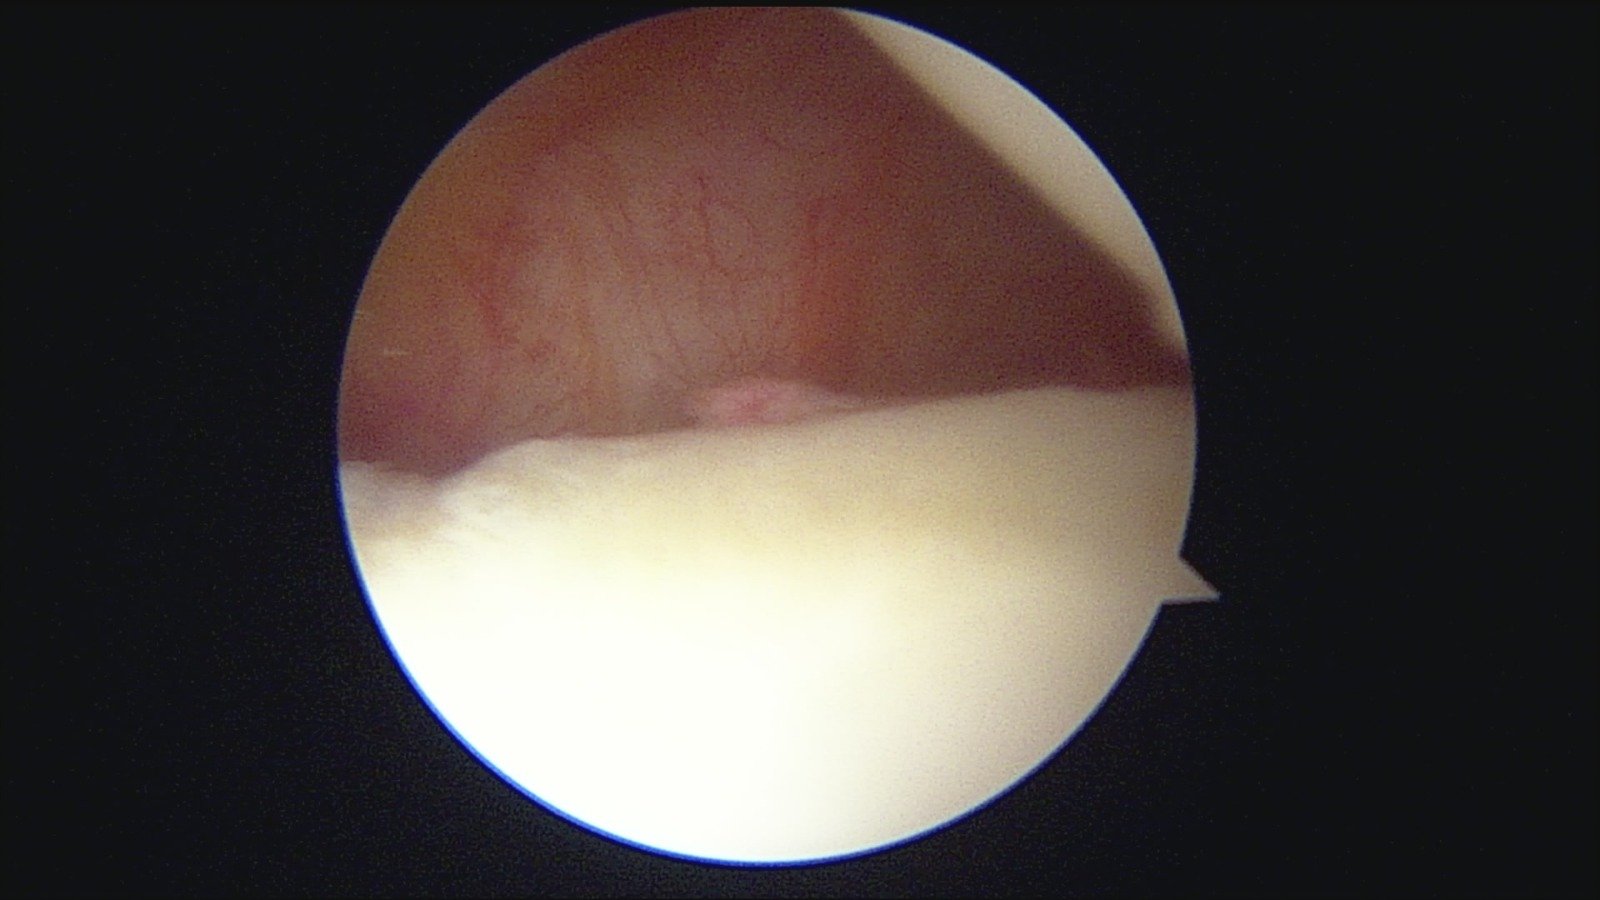

GalleryShoulder rotator cuff repair Meniscus root repair Meniscus repair Bankart repair for recurrent shoulder dislocation ACL reconstruction Machines Instruments